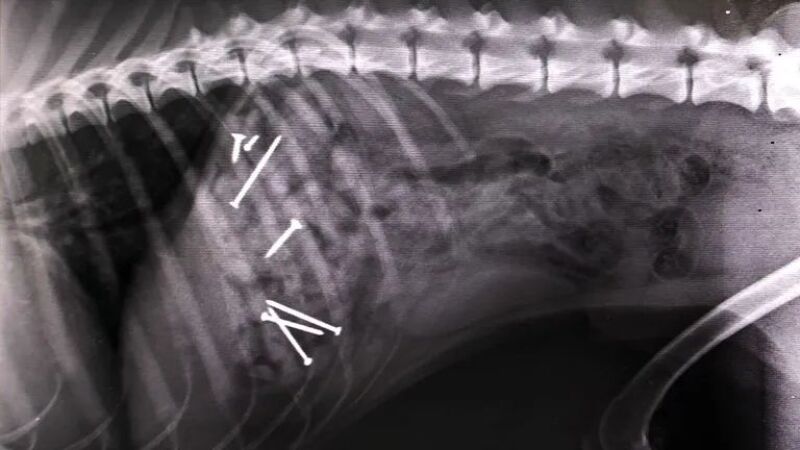

En la primera de las ubicaciones se han encontrado salchichas con clavos en su interior. Las esconden entre las hojas y el olor atrae a los perros. Cuando el animal ingiere la comida, es básico llevarlo a un veterinario para que pueda operar al can y evitar, así, la muerte. Pero no es el único cebo que se ha encontrado en los últimos días. En el Arenal la trampa va más allá.